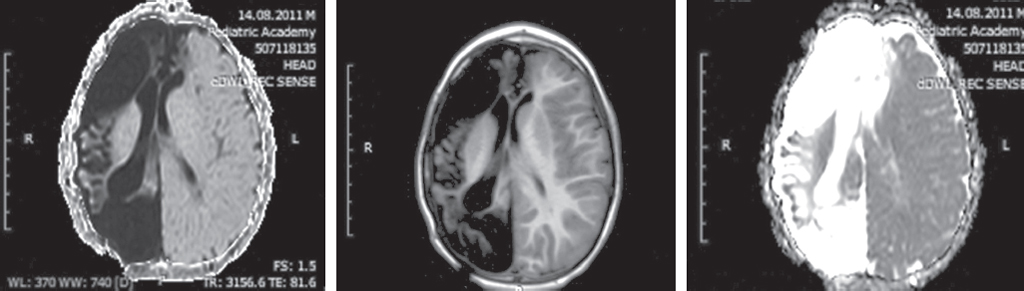

Актуальность изучения последствий геморрагических инсультов у детей раннего возраста обусловлена частотой цереброваскулярной патологии, формированием стойкого неврологического дефицита, в том числе постинсультной эпилепсии, высокой летальностью. Известно, что геморрагии диагностируют в первые 28 дней жизни у 6,7 из 100 000 младенцев, у детей с 28-го дня жизни до 18 лет — от 0,7 до 5,1 случая на 100 тыс. детского населения. Летальность при геморрагических и ишемических инсультах у детей составляет от 7 до 28 %. Эпилептические приступы острейшего и острого периода инсульта — прогностически неблагоприятные факторы течения заболевания. В статье приведены краткие литературные данные об этиологии и локализации геморрагических инсультов, их роли в формировании фармакорезистентной эпилепсии. Особое внимание уделено роли поздней геморрагической болезни новорожденных, сопровождающейся внутричерепными кровоизлияниями, в формировании структурной эпилепсии в последующем. В работе представлены также собственные клинические наблюдения 25 пациентов, страдающих эпилепсией, после перенесенного геморрагического инсульта с описанием клинической картины, особенностей пароксизмальных состояний и их терапии, данных нейровизуализации, электроэнцефалографических феноменов. Представлен клинический пример, в котором рассмотрены клинико-анамнестические, электрофизиологические данные пациента с фармакорезистентной эпилепсией, развившейся вследствие перенесенного геморрагического инсульта на фоне поздней геморрагической болезни новорожденных.

Структурная эпилепсия у детей, формирующаяся после перенесенного геморрагического инсульта, сопровождается значимыми мультирегиональными повреждениями, выраженным неврологическим дефицитом и характеризуется фармакорезистентным течением.